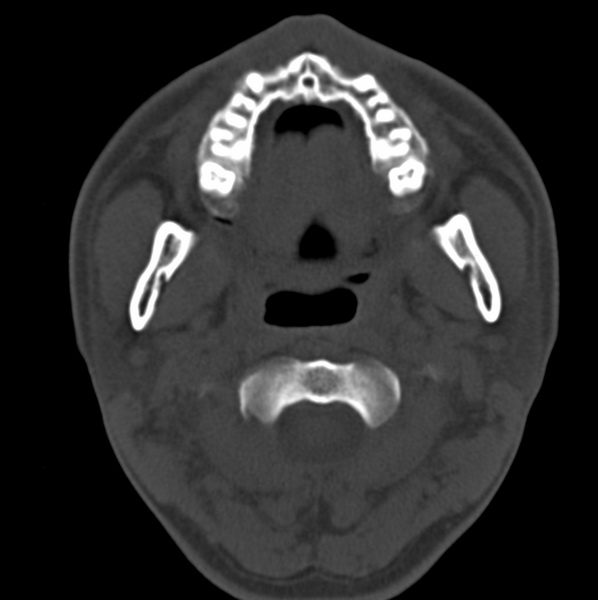

男、31、鼻咽部肿瘤放疗后请帮忙看看。

效果好,右侧破裂孔扩大,局部骨质缺损,为颅底骨质破坏。

1)鼻咽部肿瘤侵犯颅底放疗术后改变。2)左侧蝶窦炎。

咽后壁增厚,左侧咽鼓管隆突增大、咽鼓管咽口变浅,同侧咽旁间隙较窄。右侧颅底骨质破坏?为什么不在同一侧?

放疗术后改变,定期复查

鼻咽部肿瘤侵犯颅底放疗术后改变.